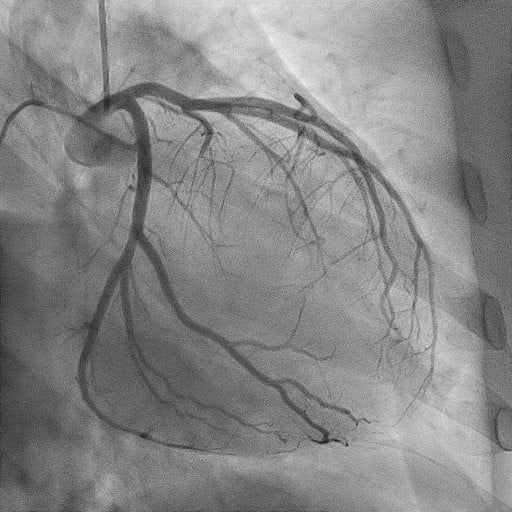

血管造影検査

当院では、血管の状態を詳しく調べたり、カテーテルを使って治療を行う「血管造影検査・治療(IVR)」を実施しています。専用の血管造影装置は2台あり、1台は心臓や足の血管など循環器専用、もう1台は脳や腹部などの頭腹部用です。令和7年4月からは、頭腹部用の装置を最新機種に更新し、より高精度で安全な検査・治療が可能となりました。主な対象疾患は、心筋梗塞、下肢動脈閉塞、脳梗塞、脳動脈瘤、頸動脈狭窄などで、これらに加え、肝臓や子宮の腫瘍、外傷などに対する止血術(TAE)など全身の病気に対応しています。経験豊富なスタッフが担当し、患者さんの負担を軽減しながら、安全で質の高い医療を提供しています。